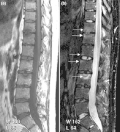

- T1-weighted semi-coronal MRI of sacroiliac joints (a) before and (b) after contrast showing active sacroiliitis (arrow).

- (a) STIR Sagittal MRI of ankle showing enthesitis at Achilles tendon insertion (thick arrow), synovitis of ankle joint (long thin arrow), and bone marrow edema at tendon insertion (short thin arrow). T1-weighted images, before (b) and after (c) contrast, show enthesitis (large arrow) and bone erosion at tendon insertion (short thin arrows).